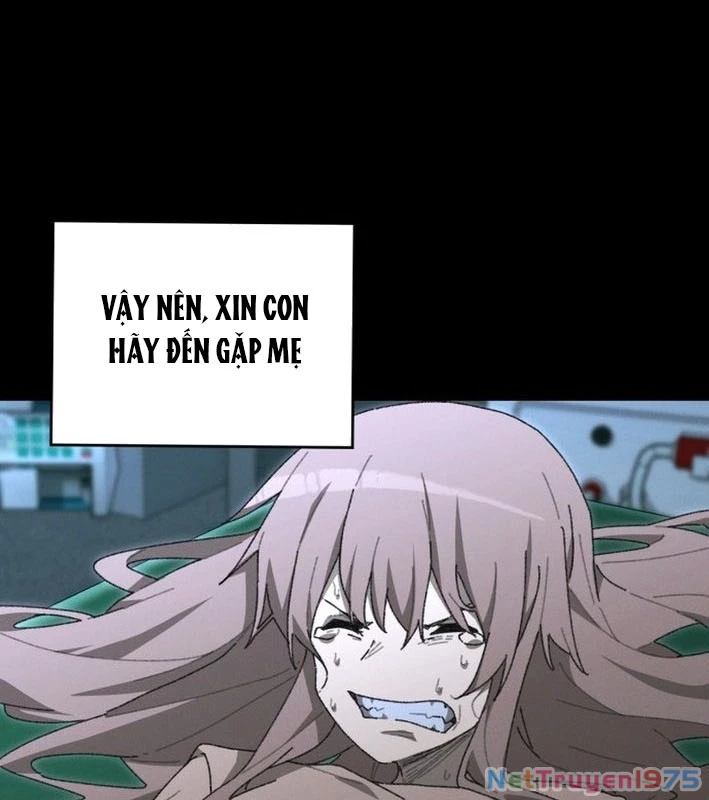

Kẻ Chôn Cất Quái Vật - Chapter 1